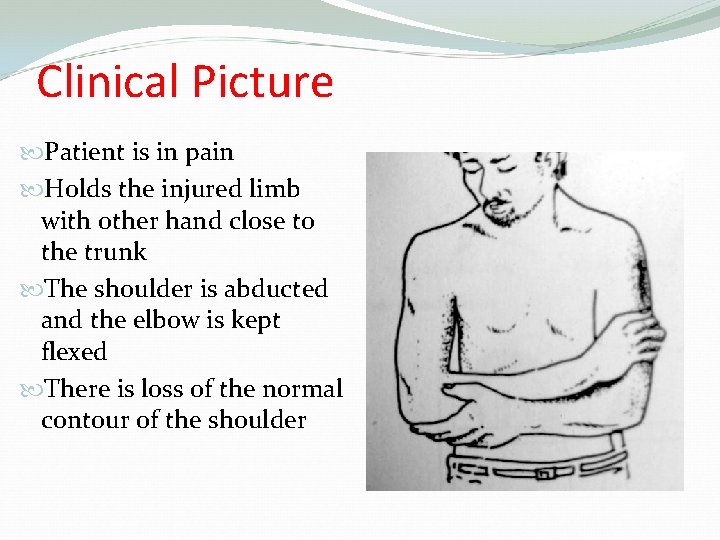

Clinical Picture Patient is in pain Holds the injured limb with other hand close to the trunk The shoulder is abducted and the elbow is kept flexed There is loss of the normal contour of the shoulder

Clinical Picture Loss of the contour of the shoulder may appear as a step Anterior bulge of head of humerus may be visible or palpable A gap can be palpated above the dislocated head of the humerus